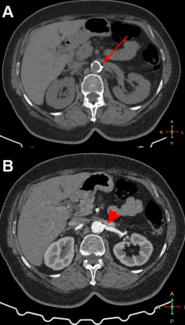

A 63-year-old woman with uncontrolled hypertension despite taking 5 antihypertensive medications was referred for percutaneous renal artery intervention.

A 63-year-old woman with...